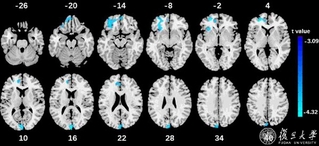

复旦科学家通过青少年脑影像学随访队列分析揭示多动症双通路模型...

近日,复旦大学类脑智能科学与技术研究院院长冯建峰教授、罗强副研究员团队,与英国剑桥大学、伦敦国王学院...